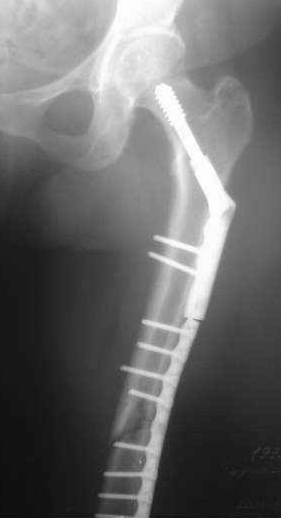

Сегодня мною была осмотрена больная, которой я выполнил накостный остеосинтез около четырех месяцев назад по поводу фрагментарного перелома бедра на уровне средней трети и межвертельной зоны.

Перелом синтезированный DHS сросся, а вот на уровне средней трети - нет. И, похоже, есть нехорошая тенденция к резорбции.

Больную беспокоит умеренный отек голени и стопы. Нагрузку на конечность не разрешаю, ибо недавно у молодого пациента при аналогичном переломе и остеосинтезе произошел перелом пластины на уровне нижней трети бедра...

Обращаясь к Александру Николаевичу, хочется узнать о целесообразности удаления металлоконструкции и интрамедуллярном штифтовании у них в институте у данной больной. Если есть резон, то нужно обговорить финансовую сторону вопроса ...